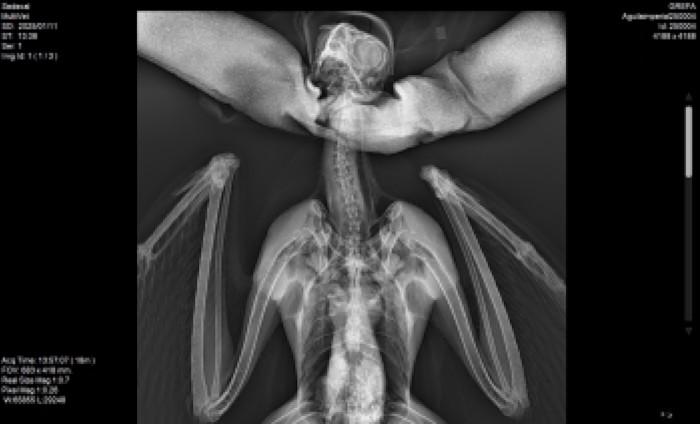

Radiografía realizada al águila imperial que ingresó hace pocos días en el Hospital de Fauna Salvaje de GREFA.

Entre los ingresos destaca la recepción el pasado 11 de enero de un águila imperial que fue trasladado a las instalaciones de GREFA por nuestro Equipo de Rescate tras recibir el aviso de la Policía de Local de Paracuellos del Jarama (Madrid), a quien agradecemos su colaboración. La rapaz fue encontrada en un camino localizado en el municipio madrileño, incapaz de volar. Tras una primera exploración, nuestro equipo veterinario pudo comprobar que el animal presentaba deshidratación, delgadez y sufría la parasitación de malófagos. A día de hoy, este águila imperial va poco a poco recuperándose.